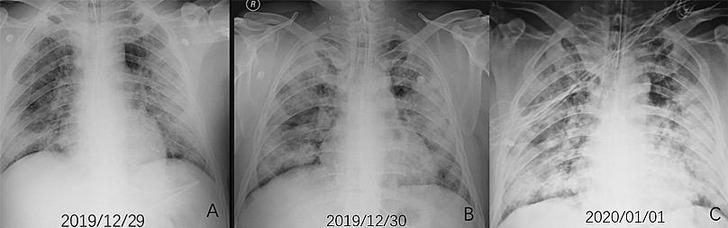

Euronews'te yer alan habere göre, koronavirüsün kaynağı olduğu düşünülen Vuhan kentindeki balık pazarında ulaşım görevlisi olan 44 yaşındaki bir erkeğin röntgen (X-ray) görüntülerindeki "opasifikasyon (buzlu cam görünümleri)" denilen beyaz lekeler, hastada oluşan zatürrenin boyutunu resmediyor.

Akut solunum sıkıntısı sendromu ve ileri derece zatürre teşhisi konulan hasta, 13 gün süren yüksek ateş ve öksürük şikayeti üzerine hastaneye başvurduktan bir hafta sonra hayatını kaybetti. Söz konusu hasta şüpheli Covid-19 vakası olarak tanımlanıyordu.